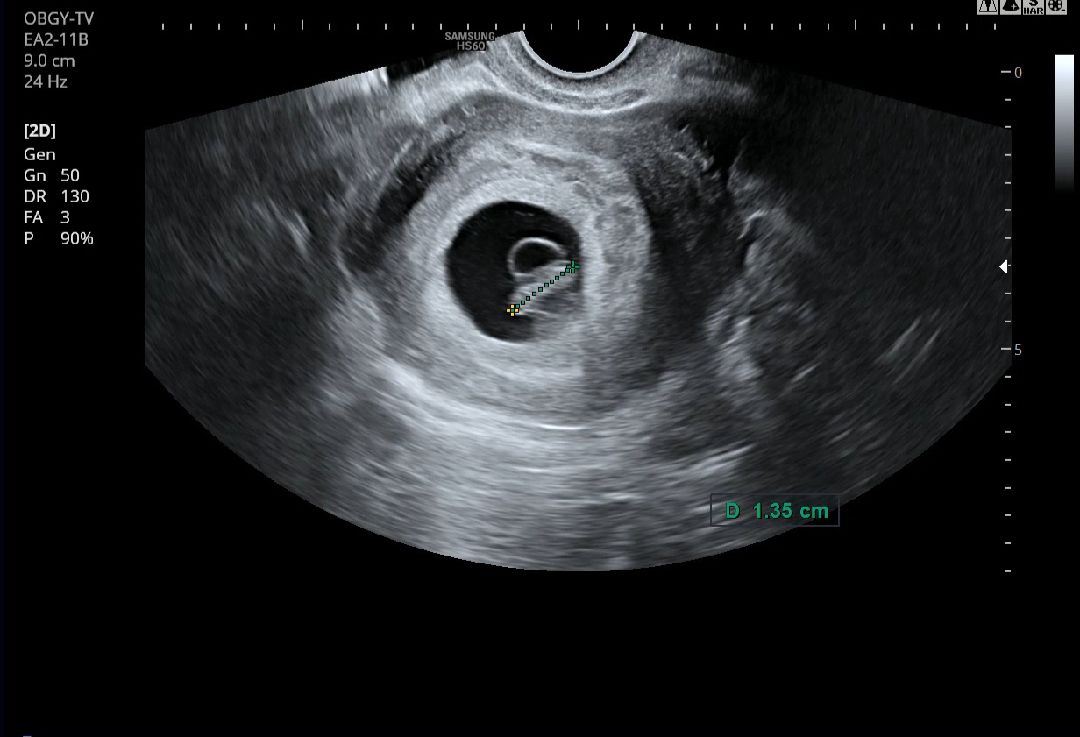

젤리곰 대신 땅콩 초음파 봤어요😆

새로운 병원에서 초진부터 받았는데 출산 예정일이 밀렸어용 ㅎㅎ 그래두 아가 건강하다고 해서 너무 좋아요😍 7주 3일차인데 아직 땅콩 모양이더라고영 🥜 그래도 너무 귀엽네요! ㅎㅎ 아가가 뱃속에서 자라고 있다는 게 참 신비로워요🙏🍀🌸🩷